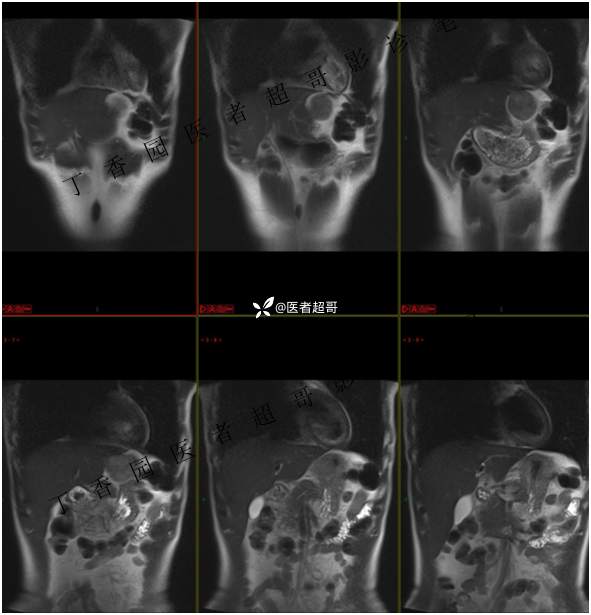

肝胃间隙肿瘤,间质瘤?平滑肌瘤?还是鞘瘤?有结果,请分析!

现病史:患者于3天前查体行肝胆脾胰肾彩超示肝内实性占位,无恶心、呕吐,无发热、寒战,无腹胀、腹泻,进一步于医院行上腹部CT增强示:肝胃交界处肿块。未行特殊治疗。今患者为求进一步治疗,来我院就诊,门诊以“肝占位性病变”收入院。患者自发病以来,神志清,精神可,饮食睡眠可,二便可,体重近期未见明显变化。